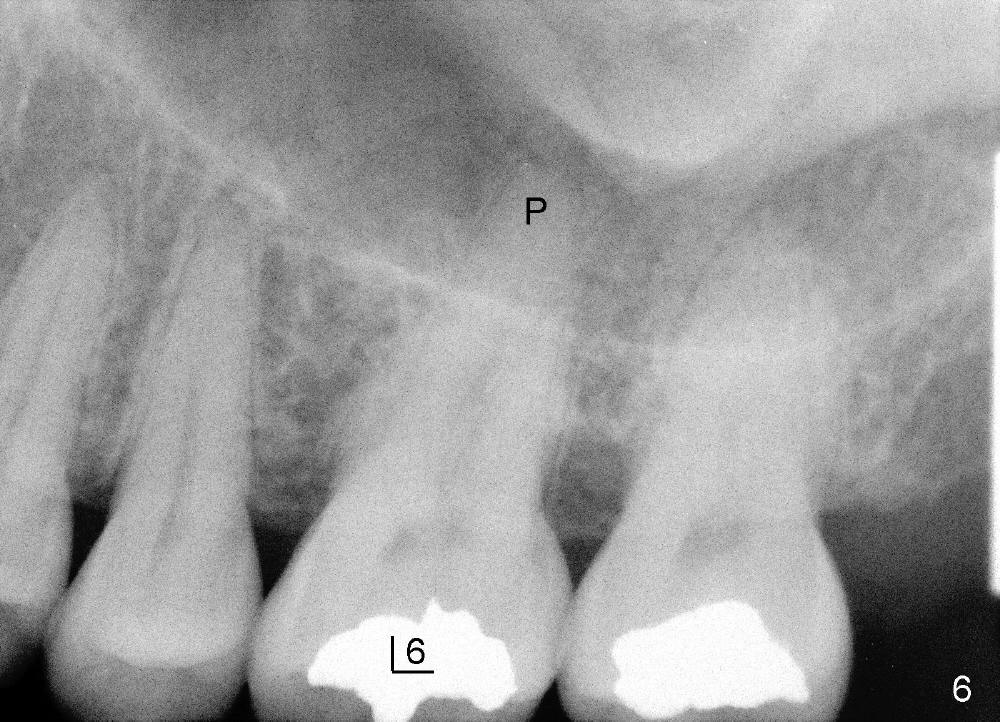

让我们再举例说明证明上颌窦中有骨质:三个月前,四十来岁女士来诊所诊治,左上六不适(图六),咬合面有一个大块银汞充填,周围有裂纹,去除银汞充填后,裂纹延伸至髓腔顶(图七),好像不到髓底,所以尝试根管治疗,但是疼痛没有消失,我们临时决定拔牙立即植牙,但是当时没有足够时间注意上颌窦底板,两眼直盯鄂侧根尖(图六:P),因此最后植牙就植入那么深(图九:I),晚上欣赏自己“杰作”时,才发现上颌窦底板(箭头),虚汗一身:一大节植牙捅进上颌窦,马上打电话给病人,她有些鼻血,但是她还不愿意回来复诊。拔牙后准备在中隔正中植牙,使用骨凿,tap形成植牙窝,后者颊侧骨壁有小面积穿孔,但是上颌窦膜还完整,最后植牙掉入鄂侧牙槽窝(图八;S:中隔;MB:近中颊侧牙槽窝;DB:远中颊侧牙槽窝),植牙很牢,torque>60Ncm。